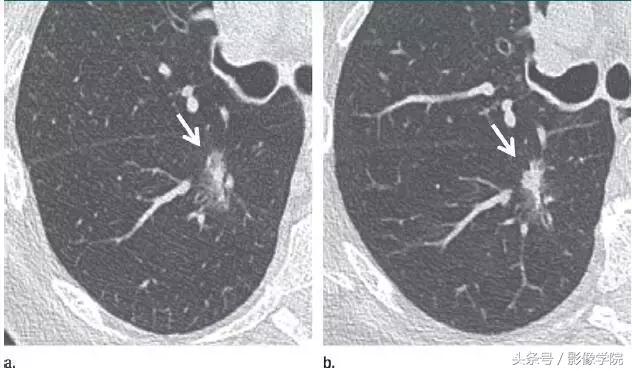

13、相隔 3 个月的结节渐进表现

图 13(a)右肺下叶上段层厚 1 mm 的 CT 横断面图像,显示一个高度可疑(较大、磨玻璃样外观和实性形态)的部分实性结节(箭头)。(b)3 个月后的 CT 随访图像显示,实性成分的大小逐渐增加。手术显示为浸润性腺癌。